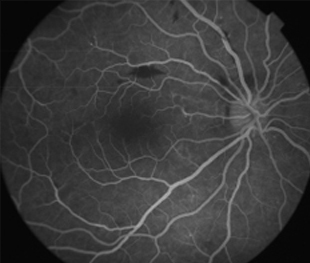

Angiografía OD

- Angiografía: teñido arterial, escape capilar, más tardíamente, no perfusion arteriolar y venular con teñido de las paredes vasculares y dilatación venosa.